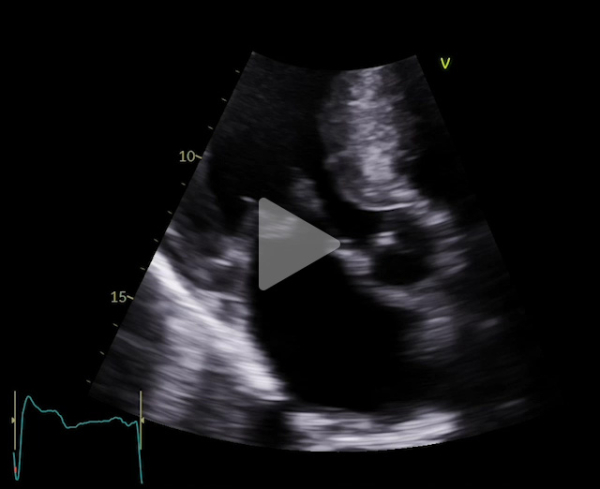

Voici son échocardiographie

Vidéo 8 : échocardiographie 2D transoesophagienne sans et avec doppler couleur en incidence 3 cavités à 120°

Vidéo 9 : échocardiographie 2D transoesophagienne sans et avec doppler couleur en incidence 3 cavités à 120°

Figure 5 : flux Doppler continu trans-aortique

Il s’agissait d’une hémolyse mécanique en lien avec l’obstruction sous aortique (Gradient max 68 mm Hg) favorisée par un SAM de la valve mitrale à l’origine de la persistance d’une IM de haut grade. On suspectait notamment un SAM de néo cordage. Un contact direct entre hématies et anneau prothétique à l’origine d’un stress mécanique est possible aussi mais plus anecdotique.

L’ETO n’avait pas retrouvé de fuite péri plastie mitrale.